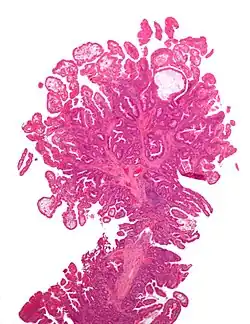

| Villous adenoma | 15%[16] to 40%[15] | Over 75% villous[14] |

| |

The villous subdivision is associated with the highest malignant potential because they generally have the largest surface area. (This is because the villi are projections into the lumen and hence have a bigger surface area.) However, villous adenomas are no more likely than tubular or tubulovillous adenomas to become cancerous if their sizes are all the same.[18]

Micrograph of a villous adenoma. These polyps are considered to have a high risk of malignant transformation. H&E stain. -